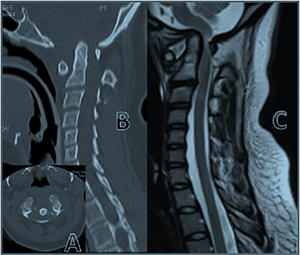

Lateral cervical radiographs showed occipito-atlantal and atlanto-

axial subluxation. Subsequent investigations confirmed

subluxation of C1/2 with an atlanto-dens interval (ADI) of 10 mm

and vertical subluxation of the odontoid process, and subluxation

of occiput/C1, with foramen magnum and spinal canal narrowing

(Fig. 1). MRI confirmed myelomalacia.

Fig. 1. Pre-operative images of a patient with Down syndrome: (A) axial CT scan at

the level of the occiput/C1 demonstrating the odontoid peg migrating into the

foramen magnum; (B) sagittal CT scan demonstrating C1 subluxation on C2 with

migration of the odontoid peg into the brainstem; and (C) sagittal T2-weighted MRI

demonstrating anterior subluxation of the occiput on C1 by 5 mm, anterior

subluxation of C1 on C2 by 11 mm, and severe canal stenosis.